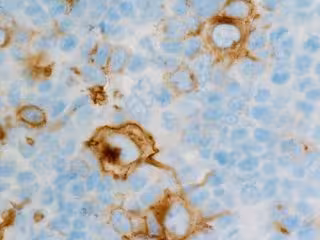

Linfoma de Hodking

FLIKR/CNICHOLSONPATH